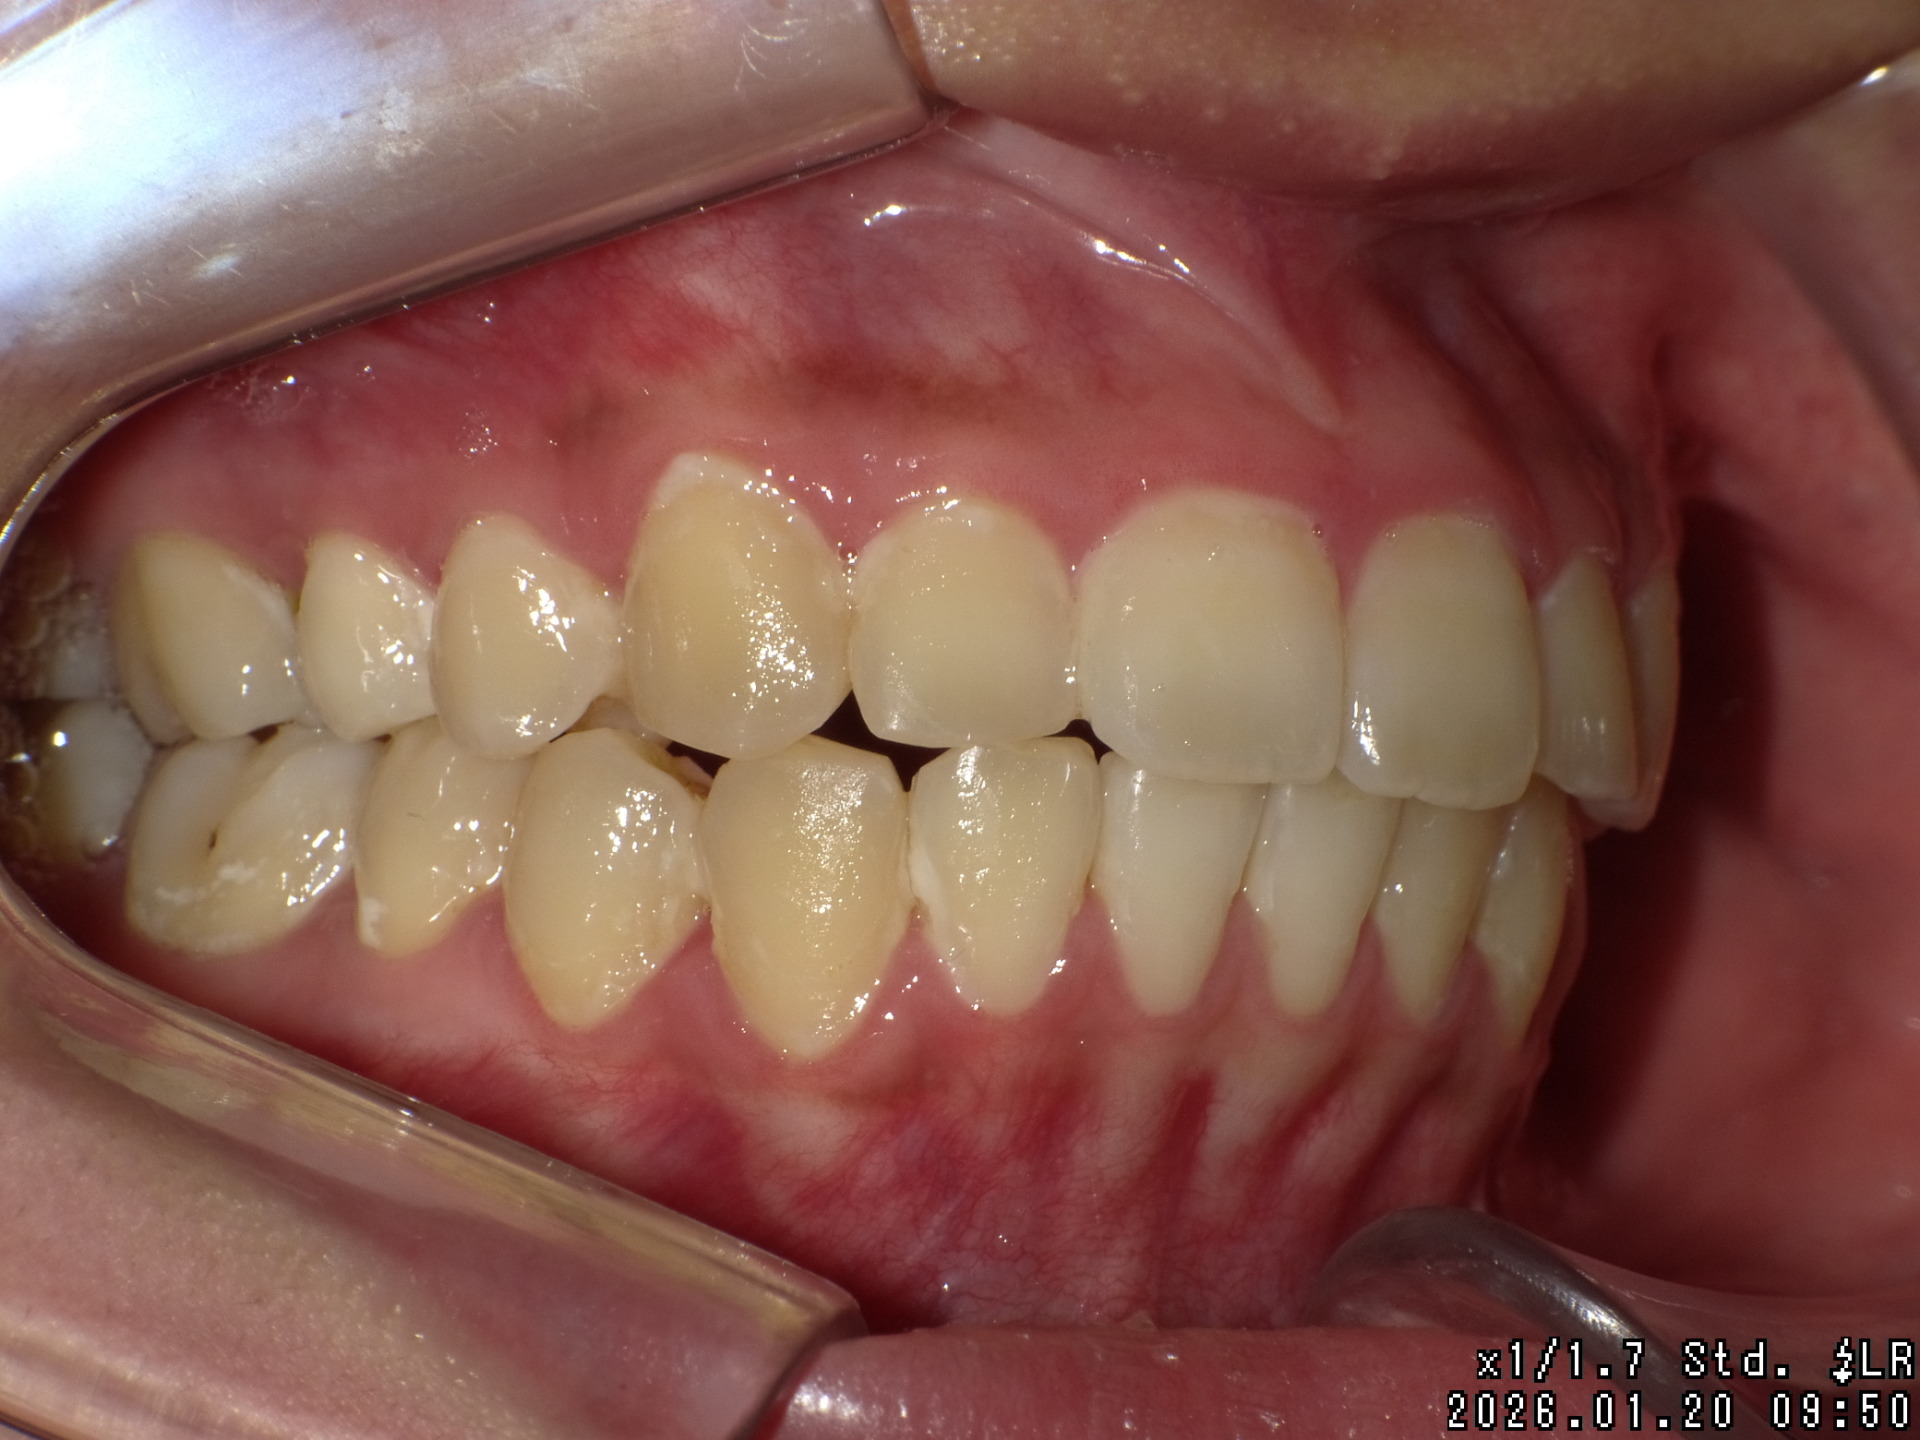

矯正後

| 症状 | 上顎前突 |

| 処置内容 | バイトブロック・プレート拡大処置・クリアアライナー・マルチブラケット装置・プレート拡大付き切歯斜面板・SHA・ディスタライザー・インビザライン |